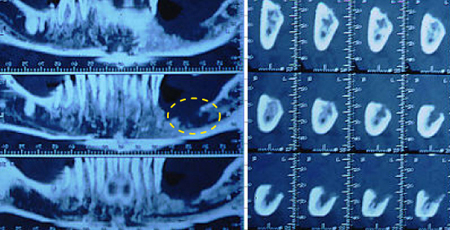

이 검사는 구강부위와 목의 림프절 전이 여부를 정밀검사 가능하게 하며, 특히 구강암에 의하여 턱뼈가 어느 정도 침범 되었는지를 판단하는데 아주 유용합니다. 최근에는 턱뼈를 1mm 간격으로 촬영하여 암의 침범 정도를 아주 정밀하게 알 수 있는 전산화단층촬영 방법도 있어 턱뼈에 암이 침범이 의심되는 경우 사용할 수 있습니다.

[전산화단층촬영]

잇몸에 발생한 구강암이 턱뼈를 어느 정도 침범했는지 덴타스캔이라는 전산화단층촬영(CT)을 이용하면 잘 알 수 있습니다.